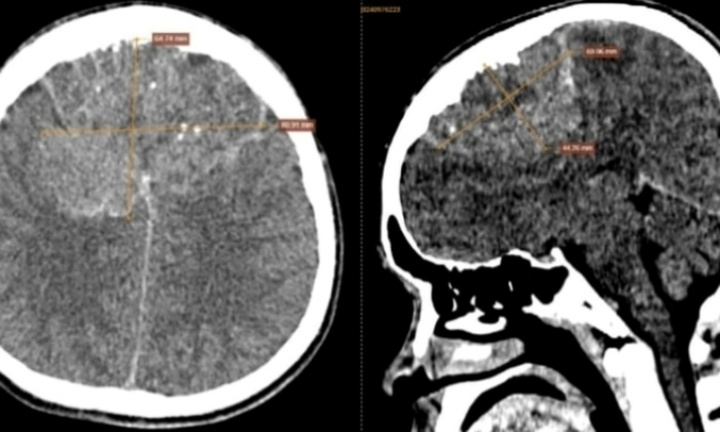

Chỉ từ một nốt mụn rộp nhỏ ở khóe miệng tưởng chừng vô hại, một phụ nữ 30 tuổi đã rơi vào tình trạng tổn thương não nghiêm trọng và không còn khả năng hồi phục.